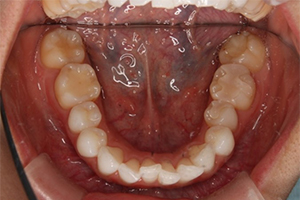

矯正治療のCASE 04

Before

After

-

- 主訴

- 歯並びがガタガタしていて清掃しにくい

- 治療内容

- ラビアル矯正(表側)

抜歯あり

- 治療費用

- 88万円~(税込)

- 治療期間

- 20か月

【リスク・副作用】

歯の痛み、口内炎、歯磨きがしにくいことによるむし歯や歯周病のリスク、歯根吸収や歯の変色、後戻りなどの副作用があります。